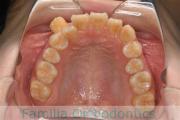

No.23V-478

- 主な症状:

- 叢生

- 年齢:

- 30歳

- 性別:

- 男性

- 抜歯部位

- 上:

- 44済

- 下:

- 8558済

- 主な使用装置:

- FEA 022

- 治療にかかった費用:

- 76万円

右上の歯が重なっているところが邪魔になるとのことで矯正治療を始められた患者さんで、札幌から転院されました。当院で約1年半、15回程度の通院が必要でした。叢生(でこぼこ、凹凸、ガタガタ)が強く、後戻りのリスクが高いケースです。